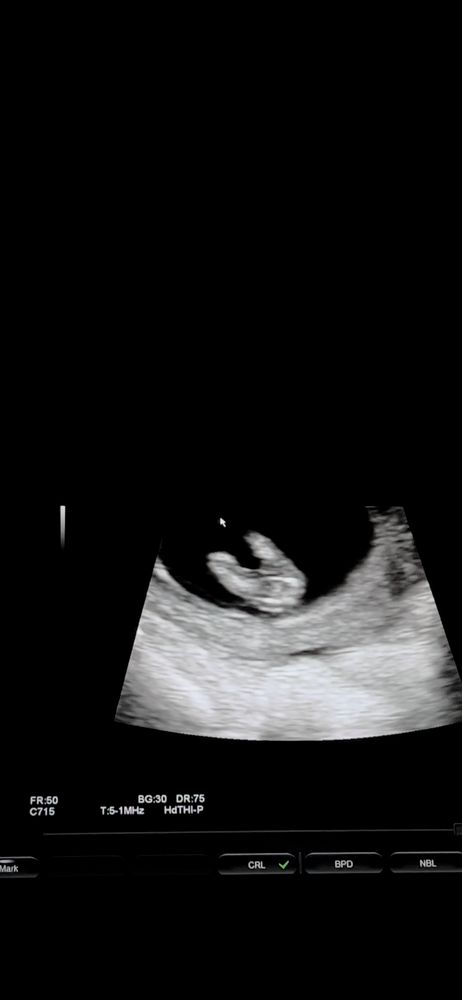

Всем привет 🤍 сегодня была на узи! 12,5недель, у меня есть 3 сына! ждём 4 малыша! Который 4,5 года к нам не приходил! сегодня снимала видео со скрининга, и думаю может можно что-то разглядеть?)) прилагаю скрины с видео , вид с боку и снизу 🤍 Благодарю за участия

Половой бугорок видно хорошо, он "торчит" практически параллельно телу, это же девчуля🥰

Похоже на девочку. Процентов на 80, как любят говорить врачи. Если на фото половой бугорок, то он параллельно позвоночнику